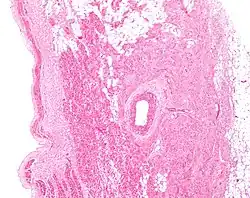

Microanatomy

The cells of the SA node are spread out within a mesh of connective tissue, containing nerves, blood vessels, collagen and fat. Immediately surrounding the SA node cells are paranodal cells.[2] These cells have structures intermediate between that of the SA node cells and the rest of the atrium.[6] The connective tissue, along with the paranodal cells, insulate the SA node from the rest of the atrium, preventing the electrical activity of the atrial cells from affecting the SA node cells.[2] The SA node cells are smaller and paler than the surrounding atrial cells, with the average cell being around 8 micrometers in diameter and 20-30 micrometers in length (1 micrometer= 0.000001 meter).[7] Unlike the atrial cells, SA node cells contain fewer mitochondria and myofibers, as well as a smaller sarcoplasmic reticulum. This means that the SA node cells are less equipped to contract compared to the atrial and ventricular cells.[8]

Action potentials pass from one cardiac cell to the next through pores known as gap junctions. These gap junctions are made of proteins called connexins. There are fewer gap junctions within the SA node and they are smaller in size. This is again important in insulating the SA node from the surrounding atrial cells.[2][8]